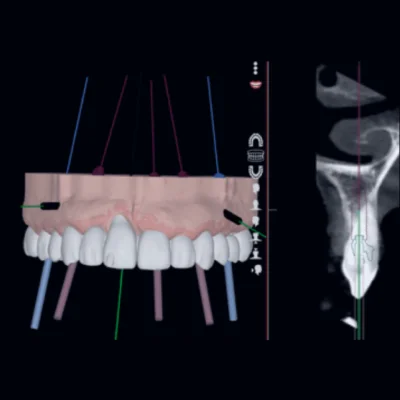

1. การวิเคราะห์และวางแผนด้วยเทคนิค NemoSmile

- ทันตแพทย์จะทำการสแกนช่องปาก (Digital Scan) และถ่ายภาพรังสี 3 มิติ (CBCT)

- นำข้อมูลทั้งหมดเข้าสู่โปรแกรม NemoSmile เพื่อวิเคราะห์โครงสร้างกระดูกและอวัยวะสำคัญต่างๆ เช่น เส้นประสาท และเส้นเลือด

- ทันตแพทย์จะจำลองตำแหน่งการฝังรากเทียมที่เหมาะสมที่สุดในแบบ 3 มิติ เพื่อความแม่นยำ

- โปรแกรมจะสร้าง Surgical Guide (ไกด์นำร่องการผ่าตัด) ซึ่งเป็นอุปกรณ์เฉพาะบุคคลที่ใช้เป็นแม่พิมพ์ในการนำทางหัวกรอระหว่างการผ่าตัด เพื่อให้การฝังรากเทียมเป็นไปตามแผนที่วางไว้